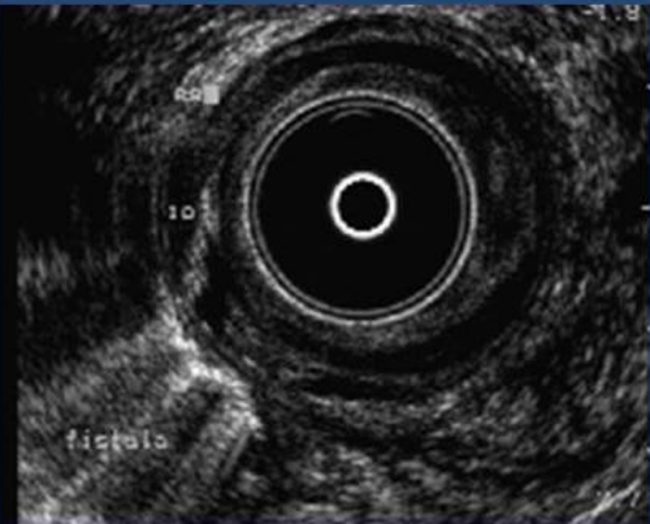

Anal fistula is an abnormal communication between an opening in…